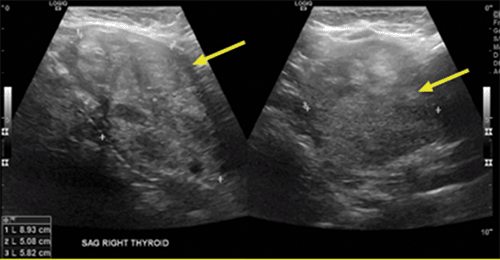

Cervical ultrasonography revealed a 5.6 cm left lobe and an enlarged right thyroid lobe measuring 9.4 cm at its largest dimension with an 8.9 cm nodule (Figure 2). On CT imaging, the right thyroid lobe measured 6.0 × 7.0 × 8.0 cm, with 6 cm of retrosternal extension reported. The trachea was deviated to the left and compressed to 9 mm in diameter. The thyroid imaging reporting and data system (TI-RADS) score for the nodule was three, based on composition and echogenicity.1 Combined with its large size, a fine needle aspiration (FNA) biopsy was performed. Cytology was consistent with a benign nodule (Bethesda II).2 It was discussed that given the extensive mediastinal extension of the goiter and the fact that the base was wider than the area at the thoracic inlet, it was possible that a sternotomy would be required at the time of thyroidectomy. Based on risks (likelihood of necessary sternotomy) and benefits, the decision was made to postpone surgery until after the delivery of her baby.

Figure 2. Cervical Ultrasound. Published With Permission

Imaging shows 5.6 × 1.3 × 1.1 cm left lobe and enlarged right thyroid lobe measuring 9.4 × 6.0 × 4.4 cm with 8.9 × 5.1 × 5.8 cm solid, isoechoic nodule. TI-RADS score of 3 based on composition and echogenicity.